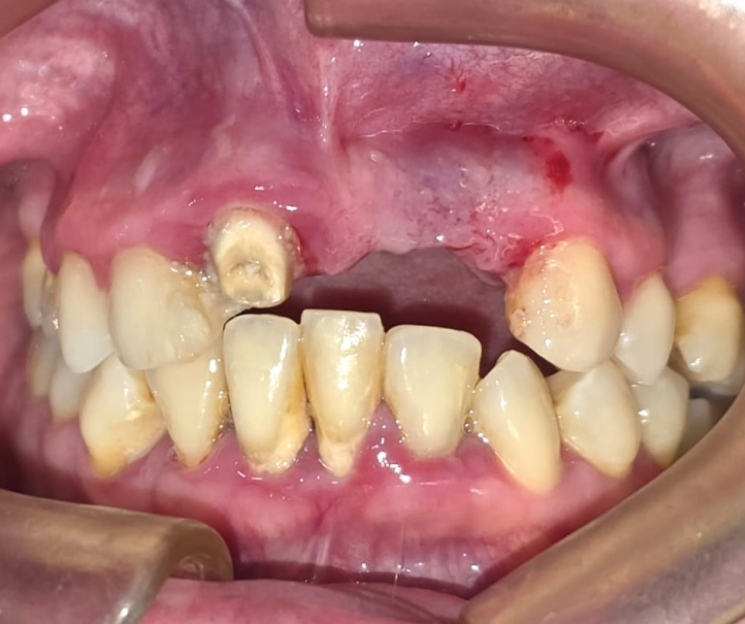

Clínica Dental especializada en la CDMX, Tijuana, Toluca, Cuernavaca, San Luis Potosí.  Colocamos  implantes dentales monofásicos de carga inmediata, también conocidos como implantes de una sola pieza. Somos una alternativa más rápida, estética y menos invasiva frente a los implantes tradicionales.

*Procedimiento: Colocación de implantes dentales monofásicos. A diferencia de los tradicionales (bifásicos), estos son de una sola pieza (tornillo y pilar integrados), lo que permite, colocar el implante y la prótesis provisional en una sola intervención o en un plazo de 3 días.

El tratamiento con implantes dentales está especialmente indicado para personas que han perdido una o más piezas dentales y desean recuperar su sonrisa a través de una solución fija, estable y definitiva, sin necesidad de prótesis removibles. Incluso aquellos pacientes que presentan poco hueso pueden ser candidatos, gracias a técnicas avanzadas que permiten trabajar con alternativas como la implantología monofásica. Además, es una excelente opción para quienes desean reemplazar prótesis removibles incómodas o poco estéticas, mejorando significativamente su calidad de vida, comodidad y confianza al sonreír.